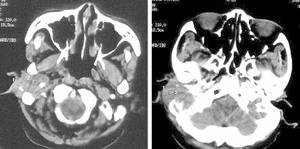

中耳癌臨床表現:血性耳漏,耳聾、耳內發脹,常為早期症狀。繼而有耳深部跳痛,向顳部和枕部放射。多數患者的中耳腔或骨性外耳道後壁有肉芽或息肉樣組織生長,堵塞耳道,易於出血。癌瘤起於鼓岬或乳突者,早期即可出現面癱、眩暈;晚期出現張口困難及第Ⅴ、Ⅵ、Ⅸ、Ⅹ、Ⅺ、ⅩⅡ腦神經癱瘓等症狀群。頸淋巴結轉移可發生於患側或雙側,亦有轉移至內臟或骨骼者。顱底頦頂位及顳骨體層X線攝片或CT檢查可示癌瘤侵蝕範圍;經病理檢查可以確診,且可依其類型選擇治療方法。此外,取外耳道分泌物作脫落細胞檢查,也有助於診斷。

中耳癌可見外耳道深部或鼓室內有肉芽樣或息肉樣新生物,質脆易出血,病檢可確診。顳骨和顱底的X線平片或CT掃描有助於確定原發部位與破壞範圍。應詳查鼻咽部以排除 鼻咽癌 。仔細查找腮腺區和頸上深處有無轉移淋巴結。預防中耳炎及對慢性化膿性中耳炎及時根治是防止發生中耳癌有效措施。

2.CT、MRI檢查 可明確腫瘤侵犯範圍。